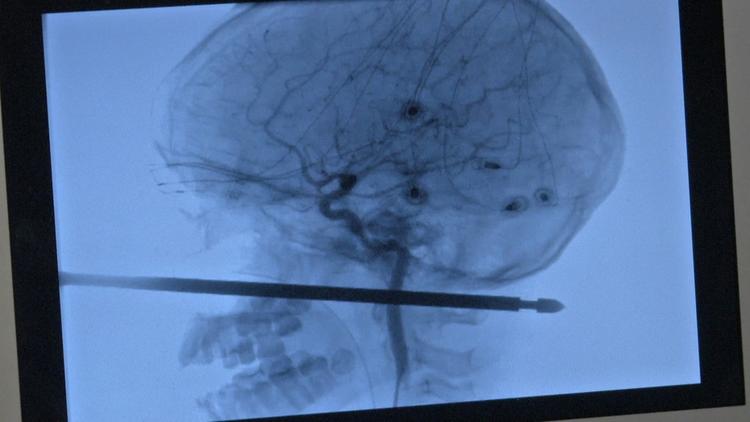

A criança brincava em uma casa na árvore, quando foi atacado por vespas e despencou com o rosto no objeto perfurante. Segundo os médicos, o espeto tinha 30 cm e destes, pelo menos 12 cm atravessaram a cabeça de Xavier, saindo na nuca.

A equipe que acompanhou e tratou o menino considerou o caso um verdadeiro milagre, já que o cérebro, os olhos , a medula e nenhum vaso sanguíneo foram atingidos na tragédia.